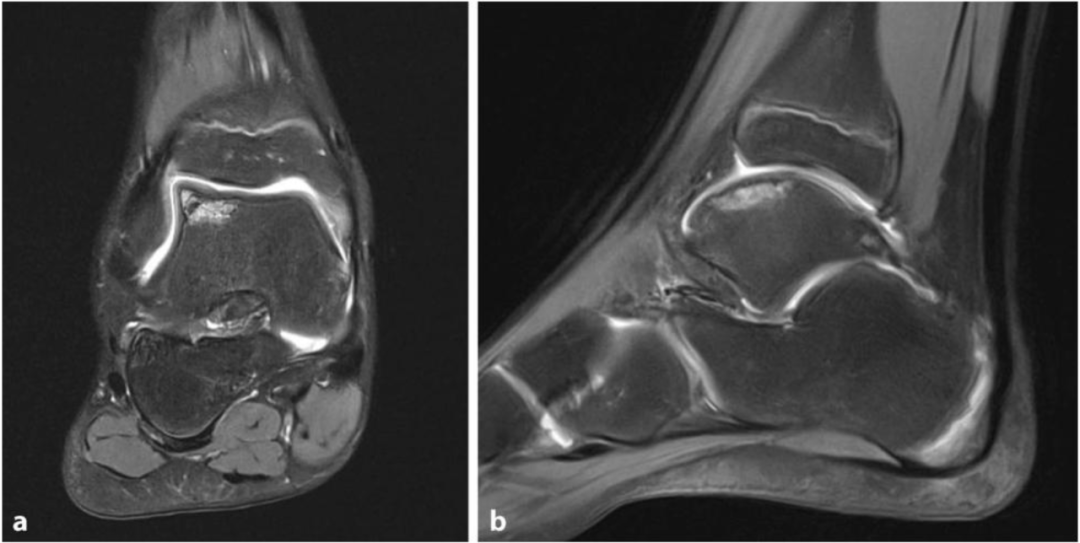

踝关节区域的非特异性疼痛或卡压感可能提示距骨骨软骨损伤(OCL)。尽管 OCL 的成因多样,但多数损伤源于既往创伤。在手术治疗中,有多种方法可用于生成替代软骨。由于这是一种针对缺损软骨的修复机制,因此存在残留症状和复发的风险。在初始保守治疗后,常需手术干预,分为关节镜和开放手术方法。其中,损伤大小(≤1cm² 或 > 1cm²)、解剖可达性、初次或翻修治疗、是否存在软骨下囊肿、伴有活骨的急性损伤或完整软骨层等因素至关重要。近年来,距骨软骨重建治疗的发展使单纯软骨成形术作为(骨)软骨损伤的单一治疗方法逐渐退居次要地位。尽管该方法也用于软骨表面不完整的损伤,但对于此类情况,已有更好的选择,因为仅通过逆行钻孔无法实现修复。MRI 诊断中看似完整的软骨表面,实际上常存在破裂,因此术前应进行关节镜检查以确认。

通过逆行钻孔实现松质骨水肿或囊肿的减压。适应症:软骨表面完整时的骨髓水肿或软骨下囊肿减压,仅限于 Berndt 和 Harty 分期的 I 期和 II 期。